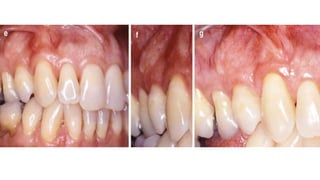

• #13 Class I gingival recessions– Baseline (a), recession depth of 3 mm (b), planning the papillary incisions (c), horizontal incisions performed as reported by Zucchelli and de Sanctis (d)

• #14 flap raised without releasing incisions (e), papillae de- epithelialization (f), flap coronally advanced and sutured as much as possible (with no tension) (g), 14-day follow-up (h), 4-month follow-up (i)